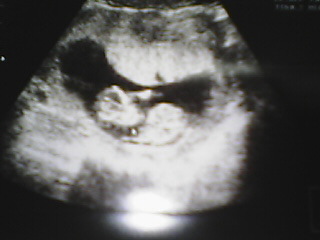

9月12日 (12w3d)

本当は日本にいるはずだったけど、まだ韓国なので、こっちでの検診。

待ちに待っていた。12週を過ぎた。

エコーをみるのが、本当に恐かった。

前回のことが、思い出された、すぐにみることができなかった。

そして、エコーに写ったあるみちゃん、大きくなっていました!!!

おまけに、手を振って、そして、仰向けから、うつぶせに・・・。

すごく元気に動いていたのーー。

感動して、また涙がでちゃったよ。